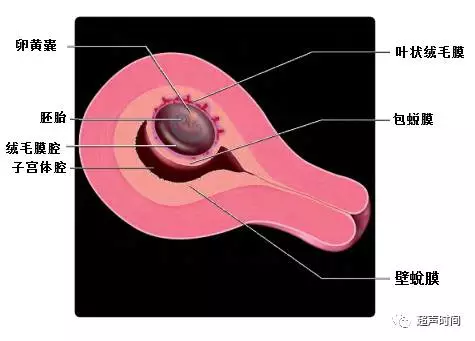

绒毛膜下血肿( Subchorionic hematoma,SCH)是指由于叶状绒毛膜出血,血液聚集在绒毛膜下与妊娠囊相间区域。借助图 1 和图 2这两张胚胎发育模式图,能帮助理解血肿的解剖位置。血肿总是在绒毛膜与子宫蛻膜之间,也就是不同大小的血肿总是在叶状绒毛膜、平滑绒毛膜与底蛻膜、包蛻膜之间。血肿与宫腔至少隔着包蛻膜,并不是在宫腔内。

图 1 胚胎发育第 6 周模式图